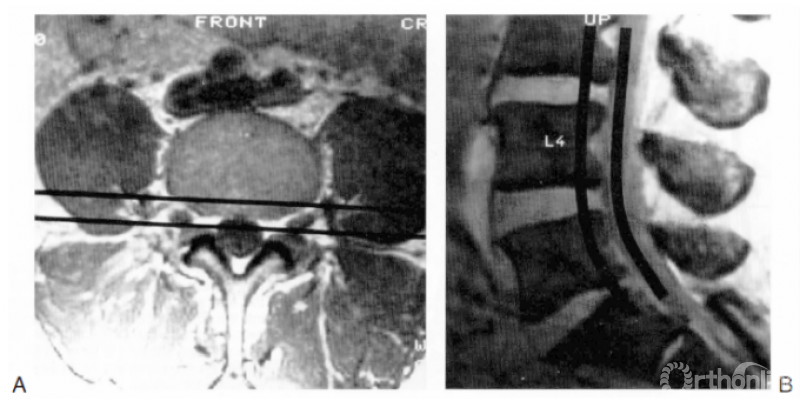

图18.7 应用3层分区法确定病变在前方椎间盘/椎体柱与后方硬膜囊之间的位置。A:横截面图像,两条黑线之间为前方椎间盘/椎体柱与后方硬膜囊的界面;B:矢状位

以椎弓根下缘作为虚拟的分割线,每个解剖节段如同一幢楼房一样可分为3层(这个概念非常清楚易懂)。接下来对各层进行判读,这样外科医生可以很准确地定位病变在椎间盘/椎体柱与神经柱间的具体位置。图18.8-18.10所示为各层病变的举例。